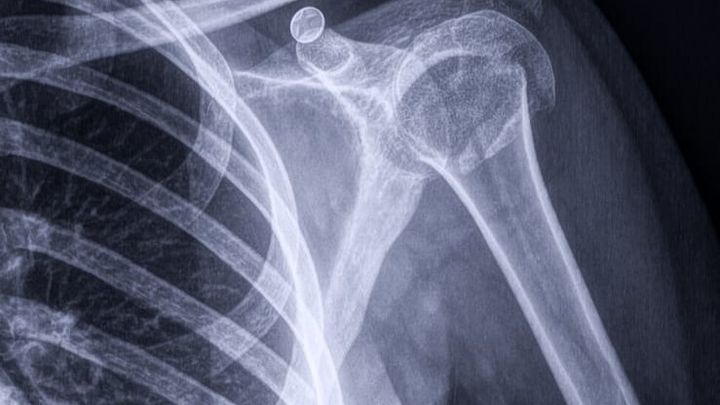

El pasado 3 de febrero, Daniela sufrió una caída que le provocó una fractura en el hombro. Tras varios estudios, se confirmó que necesita una operación urgente para no perder la movilidad de su brazo.

La cirugía está programada para el martes 17 de febrero a las 4:00 pm en el Hospital Diomed. Sin embargo, Daniela no cuenta con seguro de gastos médicos, y los costos de la operación, hospitalización y honorarios médicos son muy elevados.